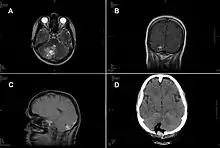

A case of intracranial T. crassiceps tapeworm cysticercosis with severe involvement of the cerebellum is described. A 51-year-old German woman was hospitalized because of progressive headache, nausea, and vomiting. The signs and symptoms had started 2 weeks before, and intensity had been increasing ever since. At the time of admission, the patient showed cerebellar ataxia but no further neurologic deficits. She did not have fever or other symptoms. She had no known chronic preconditions or recent hospital stays and had never taken immunosuppressant drugs. She had no family history of neurologic symptoms or malignant diseases. Combined surgical removal of the larvae and treatment with albendazole and praziquantel led to a complete cure in this nonimmunocompromised patient. The organism was unequivocally identified by molecular methods, thus avoiding a misdiagnosis of Taenia solium tapeworm cysticercosis.[5]